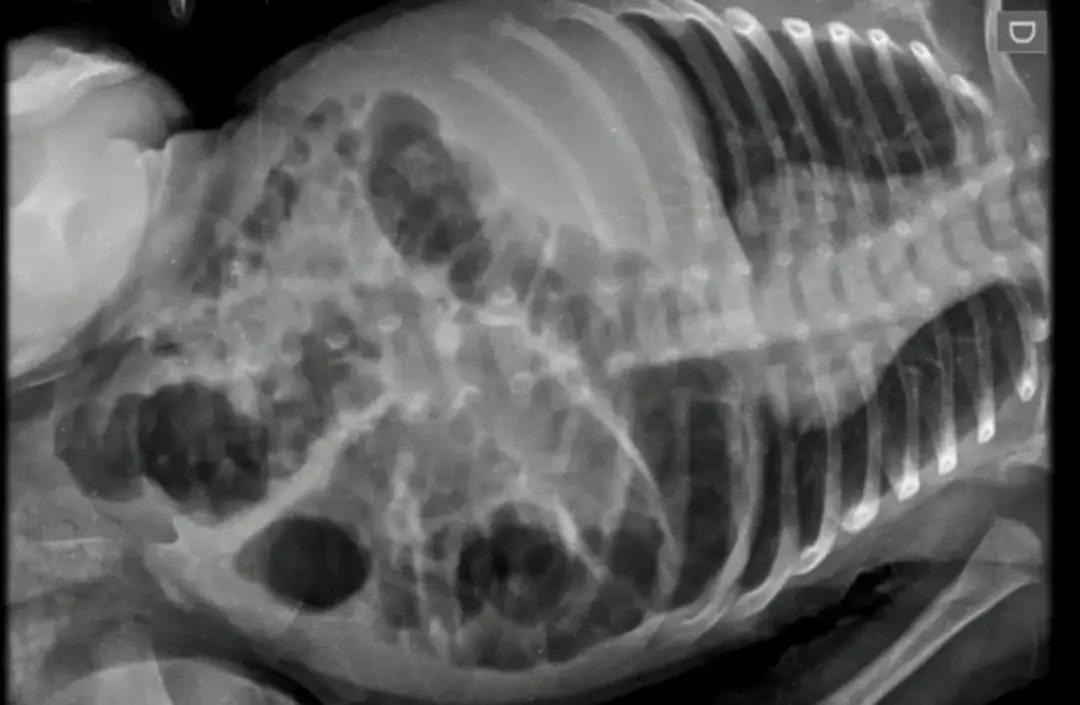

A criança sofreu lesões no rosto e barriga, além de fraturas na perna, antebraço e costelas. Segundo o delegado Rodrigo Baptista Santos, responsável pelo caso, as agravantes do crime são impossibilidade de defesa da vítima e crime praticado contra criança.

Diante do laudo do médico e do Instituto Médico Legal (IML), a Polícia Civil manteve o indiciamento. A criança sofreu ferimentos graves, se recupera bem e foi encaminhada pelo Conselho Tutelar para um abrigo do município, por determinação da Justiça.